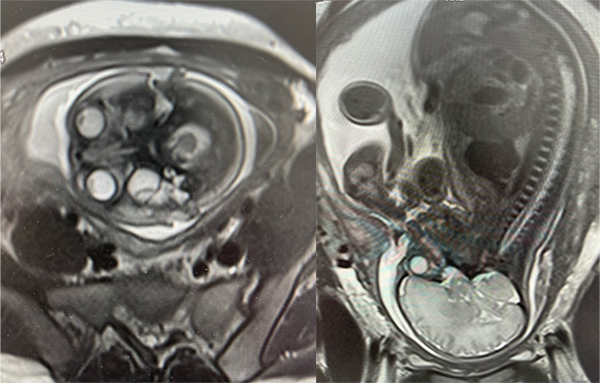

2024年10月17日,首都医科大学附属北京儿童医院成功完成了首例胎儿磁共振检查,意味着我院医学影像检查迈出了新的一步,也是对出生结构缺陷患儿从胎儿开始提供全生命周期连续性医疗服务进行影像诊疗的开端,该检查为安全、精准的早期胎儿评估、早期干预提供了强有力的技术支撑。

该患儿在外院曾进行过三次胎儿磁共振检查,均未成功。在北京儿童医院检查当天,影像中心技师骨干通过精准的操作及影像图像处理,生成了高质量的胎儿影像资料,孕妇在医技人员的细心指导下,顺利完成了磁共振扫描。整个检查过程中,设备运行平稳,清晰地显示了胎儿相关检查部位的解剖结构,图像采集迅速高效,为后续的临床决策提供了重要依据。

胎儿磁共振检查(Fetal MRI)作为一项非侵入性诊断技术,其独特优势在于无电离辐射的情况下,可清晰呈现胎儿体内结构,尤其是对胎儿中枢神经系统、肺部、心脏等复杂器官的发育情况提供高分辨率图像。北京儿童医院影像中心采用的先进磁共振检查设备,提供了高质量的图像与更低的噪声干扰,可为临床医生提供了更为详尽、准确的信息。